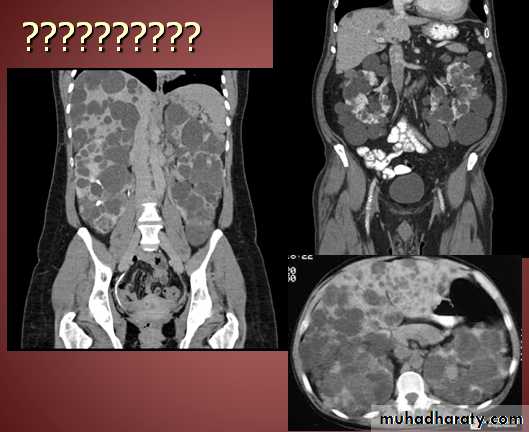

Secondary metastasis in the liver

Multiple rounded hypo density areas of different density , shape & different size .

Pattern of enhancement is either uniform , target or bulls eye pattern .

Hepato megaly .

Secondary metastasis within the liver